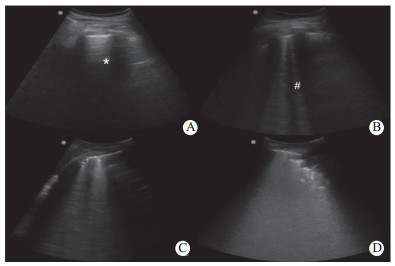

1.2 肺部超声评估患者入院第1天至患者入院第7天,每间隔1 d,由不知晓患者病情并经过专门急危重病超声培训的医师使用SonositeTurbo型便携式超声仪(美国索诺声公司,宽频弧形探头,2~7MHz),快速截取患者双侧供12个BLUE点的肺部超声影像(呼气末,共12个点),并在超声机上储存图像,由操作者及不知晓实验设计的另2位同样经过专门急危重病超声培训的医师对存储的图像进行肺超声评分(lung ultrasound score,LUS)。检查区域见文献[10]。LUS评定分为4个等级:(1)正常通气:表现为平滑的A线或者少于2条孤立的B线(记0分);(2)中度肺通气减少:大量的清晰B线(间距大于7 mm,B1线)(记1分);(3)重度肺通气减少:大量临近(间距<3mm)或融合的B线(B2线)(记2分);(4)肺实变:表现为具有动态的支气管充气影的组织(记3分)。正常肺部超声评分总分为0分,最高为36分。最后每个时点的LUS值采用3位医师的平均值而得出(图 1)。

| (A)正常通气区,为肺滑动征伴A线(*)或少于2个单独的B线(#),0分;(B)中度肺通气减少区,影像为多发、典型B线(B1线),1分;(C)重度肺通气减少区,为多发融合的B线(B2线),2分;(D)肺实变区,见组织影像伴典型的支气管充气征为3分 图 1 肺部超声评分(LUS) |